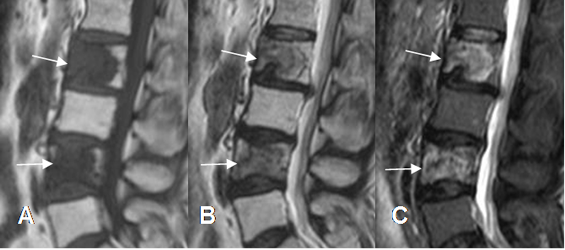

Fig 228 A. Metástasis mixtas.

A: RM sagital en T1, B: RM sagital en T2 y C: RM sagital en STIR. Igual paciente anterior. Alteración en la señal de L2 y L4, hipointensas en T1 y T2 e hiperintensas en STIR, por metástasis mixtas de neoplasia de mama.